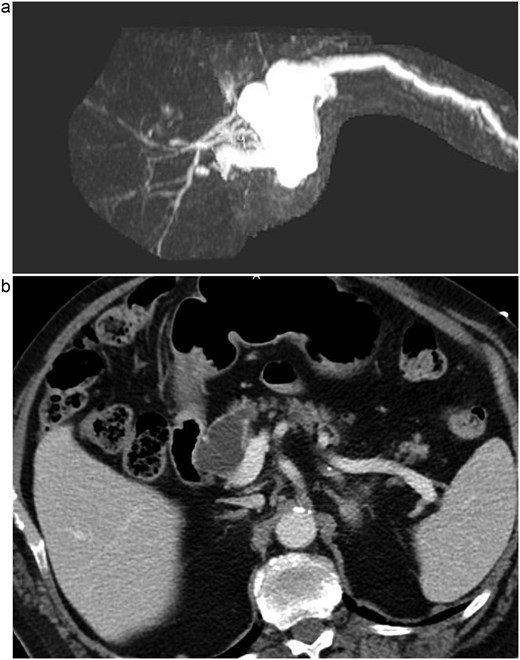

Post-operatively, NGT removal was delayed to post-op day (POD) 3 due to persistently high output. The patient required daily enemas, and his first bowel movement was on POD 7. He was gradually advanced to a low-fat regular diet, while JP drains remained serosanguinous with low drain amylase levels. Unfortunately, he developed a fever of 102.5°F on POD 9 and sudden onset abdominal pain. CT imaging showed a 6 cm fluid collection posterior to the PJ, a persistently dilated stomach, and a high colonic stool burden. An NGT was replaced and total parenteral nutrition initiated. The patient then underwent IR guided aspiration and drainage of the fluid collection within 24 h of symptom onset. After percutaneous drainage, the patient improved clinically. However, ~12 h after drain placement, the drainage changed from purulent to bilious in color. Repeat CT imaging demonstrated that the IR drain had ultimately been positioned within the lumen of the blind end of the afferent limb (see Fig. 3).

CT images of this patient’s post-operative pancreatic fistula (a) prior to IR guided intervention; (b) after percutaneous jejunostomy that was confirmed to rest within the blind jejunal end of the afferent loop after pancreaticoduodenectomy.